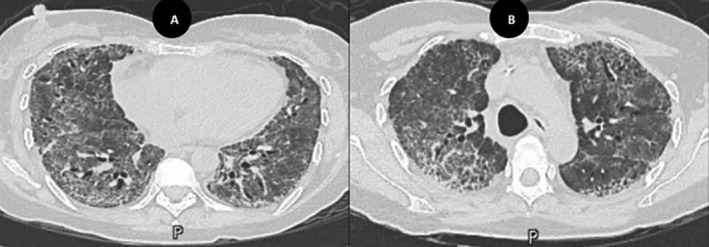

Bleomycin-induced lung injury (BILI) is a well-recognised but potentially life-threatening complication of ABVD chemotherapy (adriamycin, bleomycin, vinblastine and dacarbazine), often requiring prompt diagnosis and intervention. We present a case of a 43-year-old female with Hodgkin's lymphoma who developed progressive respiratory symptoms following her fourth cycle of ABVD. A broad infectious and autoimmune workup was unremarkable, and chest imaging was consistent with interstitial lung disease. Her condition deteriorated despite empirical antibiotics and high-dose corticosteroids. The addition of rituximab and pirfenidone led to significant clinical and radiological improvement, highlighting the potential role of these agents in managing steroid-refractory BILI.